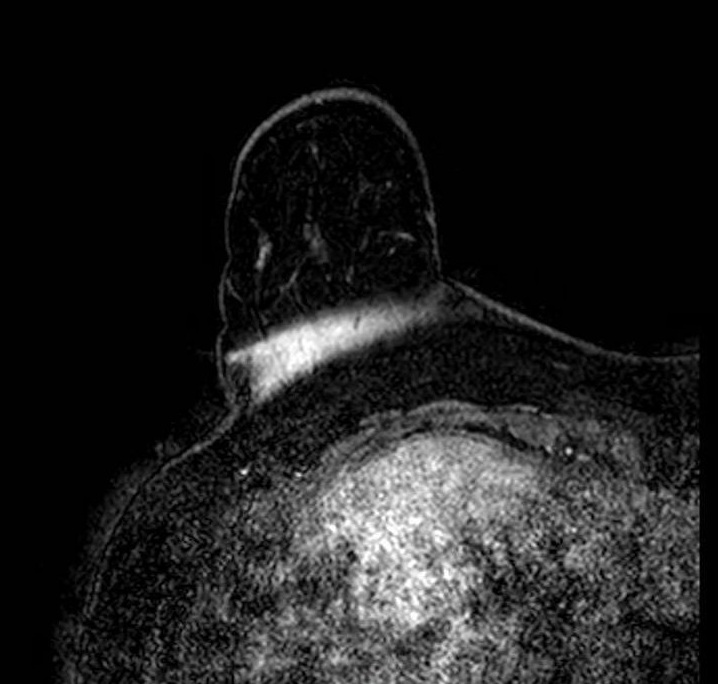

Partial Volume / Breast Fold

Partial volume artifact at a breast fold. Sagittal image shows abrupt signal change where tissue curves back on itself, creating a plane of partial volume averaging and an artifactual interface. The breast remains within the FOV; the effect reflects mixed tissue signal within single voxels at the fold. The appearance changes across adjacent slices as the fold geometry shifts through the stack.